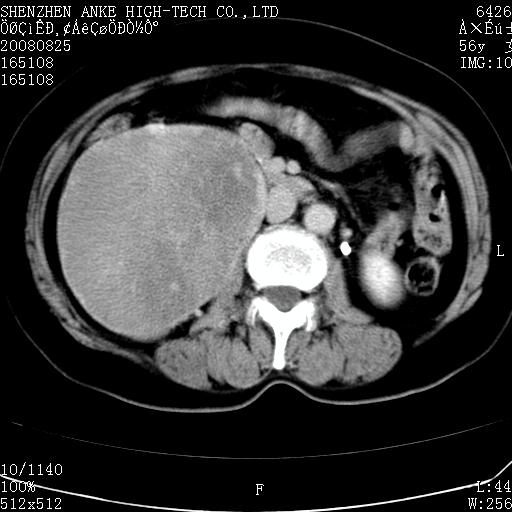

患者,女性,56岁,腰痛3年,查:右腹部约8x10cm肿块,固定,无压痛;8月23日在外院做了平扫,发现右肾巨大肿块(外院具体诊断不祥);今天在我院做了静脉肾盂造影,示:右肾明显增大,分泌功能明显减弱。

右肾癌可能大。

右肾癌

右肾占位、癌可能性大。

支持右巨大肾癌。

1)考虑右肾癌并右肾静脉瘤栓形成。2)脂肪肝。